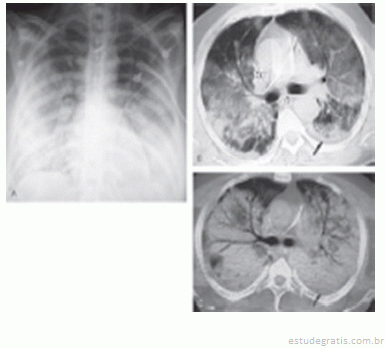

O conjunto de imagens abaixo representa o diagnóstico de:...

O conjunto de imagens abaixo representa o diagnóstico de: